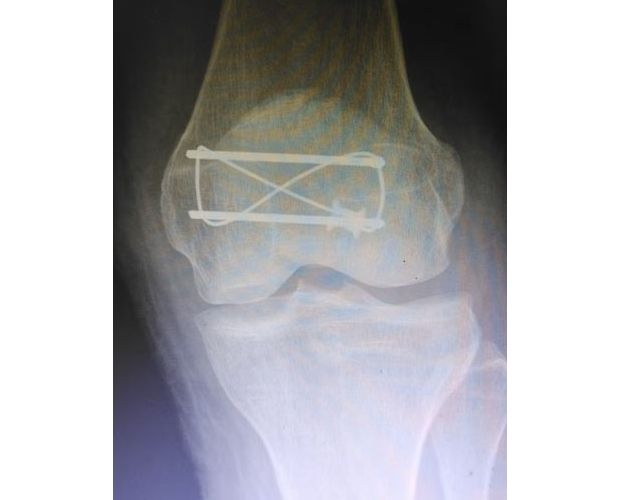

精湛施術 安全有序,守護患者健康

手術現場,徐三軍主任憑借多年積累的臨床經驗和嫻熟的手術技巧,精準完成骨折復位、鋼板內固定、傷口縫合等一系列關鍵操作,動作規范流暢、精準高效,最大限度減少手術創傷。該院外科醫護團隊全程密切配合、協同發力,嚴格按照手術規范操作,全程嚴密監測患者心率、血壓等生命體征,及時應對術中各類突發情況,全力保障手術安全。此次手術全程順利,術中出血量少,患者生命體征始終平穩,術后患者順利安返病房,為后續康復治療奠定了堅實基礎。